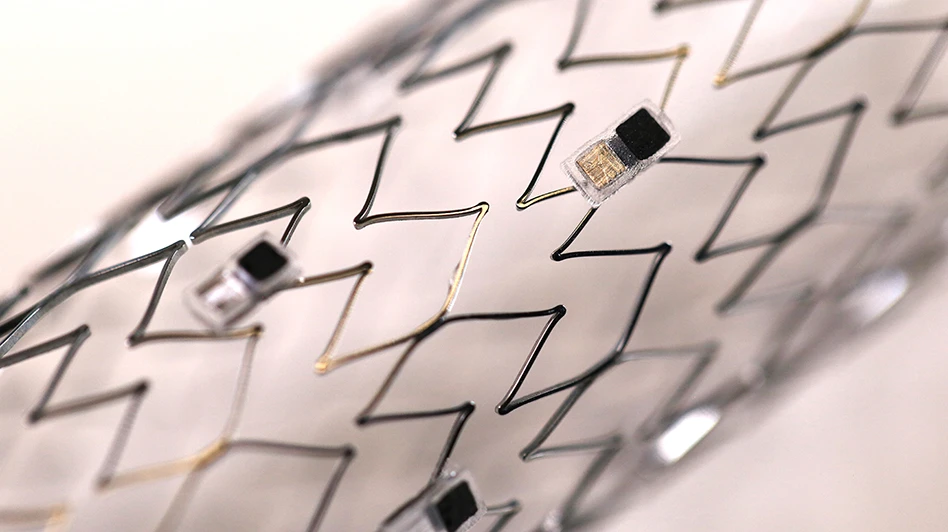

- Hacker-proofing smart implants